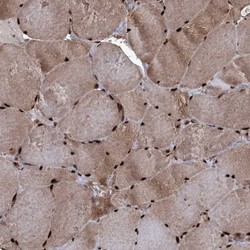

Immunohistochemistry

NBP1-85548 IHC